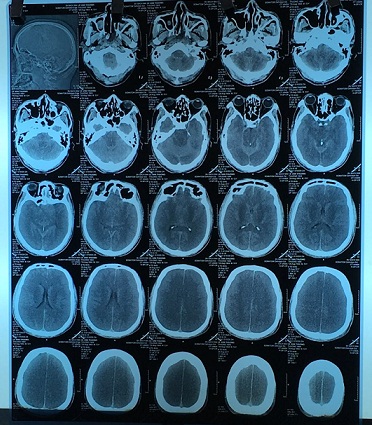

Ngày 26/8, Trung tâm Chống độc, Bệnh viện Bạch Mai đã tiếp nhận một bệnh nhân ngộ độc methanol rất nặng. Bệnh nhân là anh Lê Văn T, sinh năm 1954, ở Vĩnh Tiến, Vĩnh Lộc Thanh Hóa.ThS. BS. Nguyễn Trung Nguyên, Phụ trách Trung tâm Chống độc cho biết: do nghiện rượu  nên anh T. mua cồn ở hiệu thuốc về uống thay rượu. Đó là cồn sát trùng loại 500 ml. Khi bệnh nhân nhập viện đã trong tình trạng hôn mê, tụt huyết áp, dấu hiệu nhiễm toan nặng, rất điển hình của ngộ độc methanol. Kết quả chụp phim cho thấy: não bị phù, căng  cả 2 bên. Dấu hiệu gợi ý nhu mô não tổn thương nặng và lan rộng cả 2 bên. Nồng độ methanol trong máu là 210 mg/dL (gấp nhiều lần so với nồng độ gây tử vong, khoảng 40 – 50 mg/dL đã là rất nặng). Bệnh nhân đã được cấp cứu, hồi sức, lọc máu thải độc, dùng các thuốc giải độc nhưng do đến muộn và não tổn thương quá nặng, tử vong cận kề nên gia đình xin về để mất tại nhà.

hinh anh nao Bn ngo doc methanol

Hình ảnh phim chụp não của bệnh nhân bị ngộ độc methanol nặng